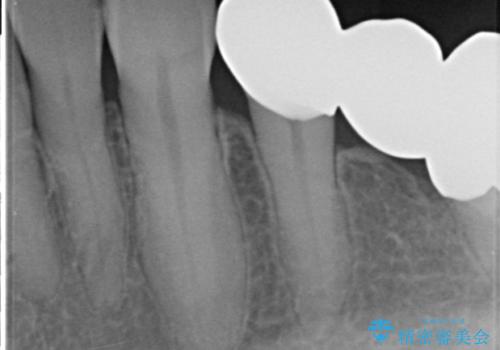

手術後に根管治療を行い、歯肉と骨の治癒を十分に待った後ブリッジによる補綴治療を行いました。

ご希望通り歯を抜かずに残すことができ、喜んで頂けました。

セルフメンテナンスしやすいよう、ブリッジと歯ぐきの間に歯間ブラシを通すことができるように作製しています。

咬合関係により奥歯の負担が大きいため、今後も注意深く経過観察していく予定です。